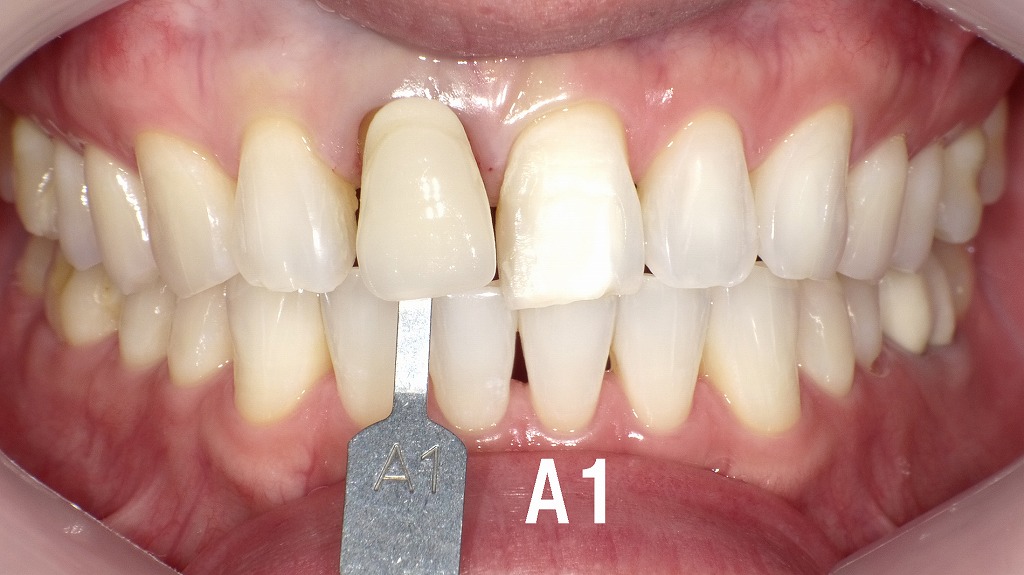

この写真はホワイトニング後の前歯部の口腔内です。

右上1番(上の前歯の右側)はすでに根管治療後で、ファイバーコア(土台)が装着されています。最終的にはこの歯にオールセラミッククラウンを装着予定であり、ホワイトニング後の明るい歯色に合わせた自然な仕上がりを目指しています。

全体的に歯列は整っており、歯肉の健康状態も良好です。今後、オールセラミックを装着することで、審美性・透明感・色調の調和がさらに向上する予定です。